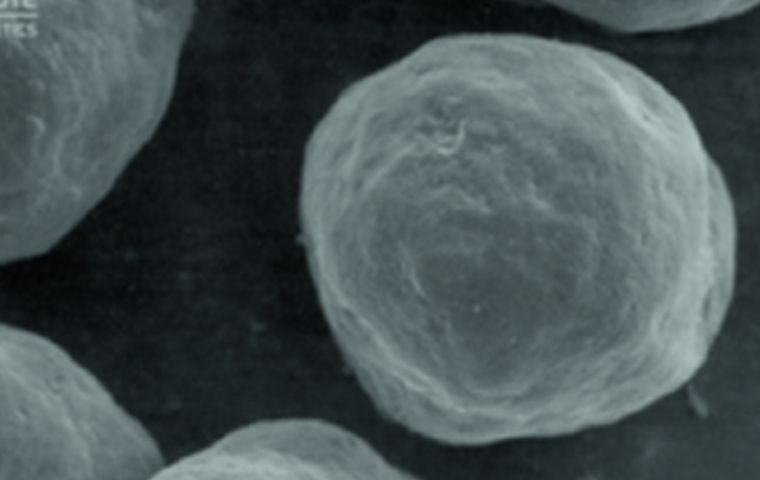

수용성 겔 캐리어와 미세한

CaHA(칼슘 하이드록시아파타이트) 입자로

구성된 칼슘 미네랄 필러입니다.